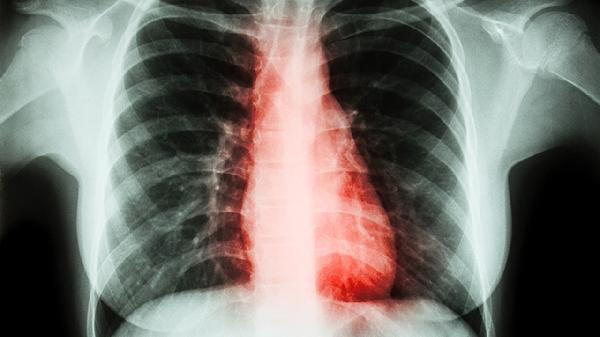

3、气短或呼吸困难:

这是最具特征性的症状,早期仅在劳力时出现,后期逐渐加重,以致日常活动甚至休息时也感到气促。呼吸困难呈进行性发展,患者常描述为"呼吸费力"、"气不够用"或"喘息"。症状严重程度与肺功能损害程度相关,但个体差异较大。

4、胸闷:

患者常主诉胸部压迫感或紧缩感,尤其在活动后明显。胸闷可能由肺过度充气、膈肌低平导致呼吸效率下降引起。部分患者会将胸闷误认为心脏问题就诊,实际上这是气道阻塞和气体陷闭导致的典型表现。